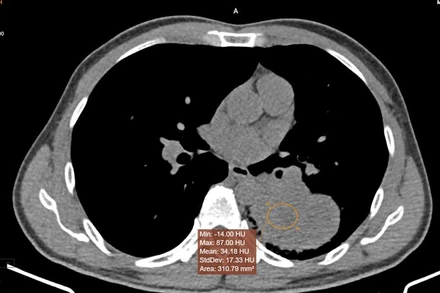

Việc ứng dụng AI vào phân tích, xác suất nốt kính mở ở thùy trên phổi trái trên phim chụp CT là tổn thương ác tính khoảng 97%, bệnh nhân được chẩn đoán ung thư phổi và được can thiệp ngay từ sớm.